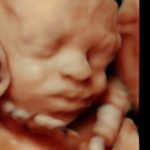

4D/5D/HD Ultrasound Gallery

Gallery